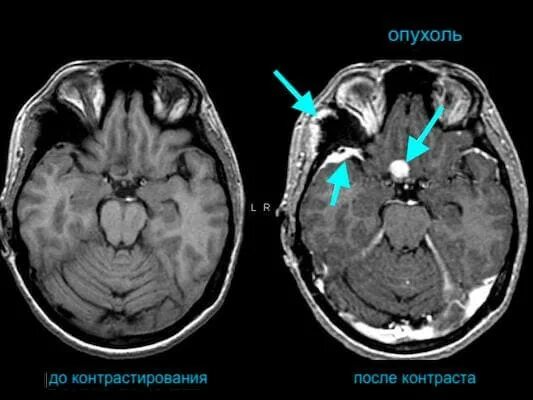

Мрт с контрастированием головного